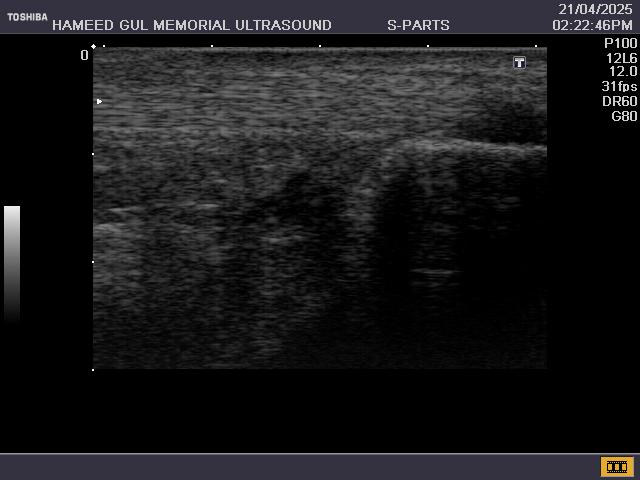

Ultrasound of the musculoskeletal system helps diagnose

A. Examination of the knee joints for muscle injuries, collateral ligament injuries, patellar tendon pathologies, joint effusions, Baker’s cyst, popliteal artery aneurysm.

B. Shoulder joint for evaluation of the rotator cuff pathologies including impingement and rotator cuff tears.

C. Ankle joint for ruptured achilles tendon or ankle effusions.

D. Ultrasound of various tendons to assess acute or chronic tendonitis.

E. Ultrasound of various bursas for acute and chronic bursitis and

F. Assess soft tissue masses for example haematomas, abscesses, neoplasms and muscle tears.